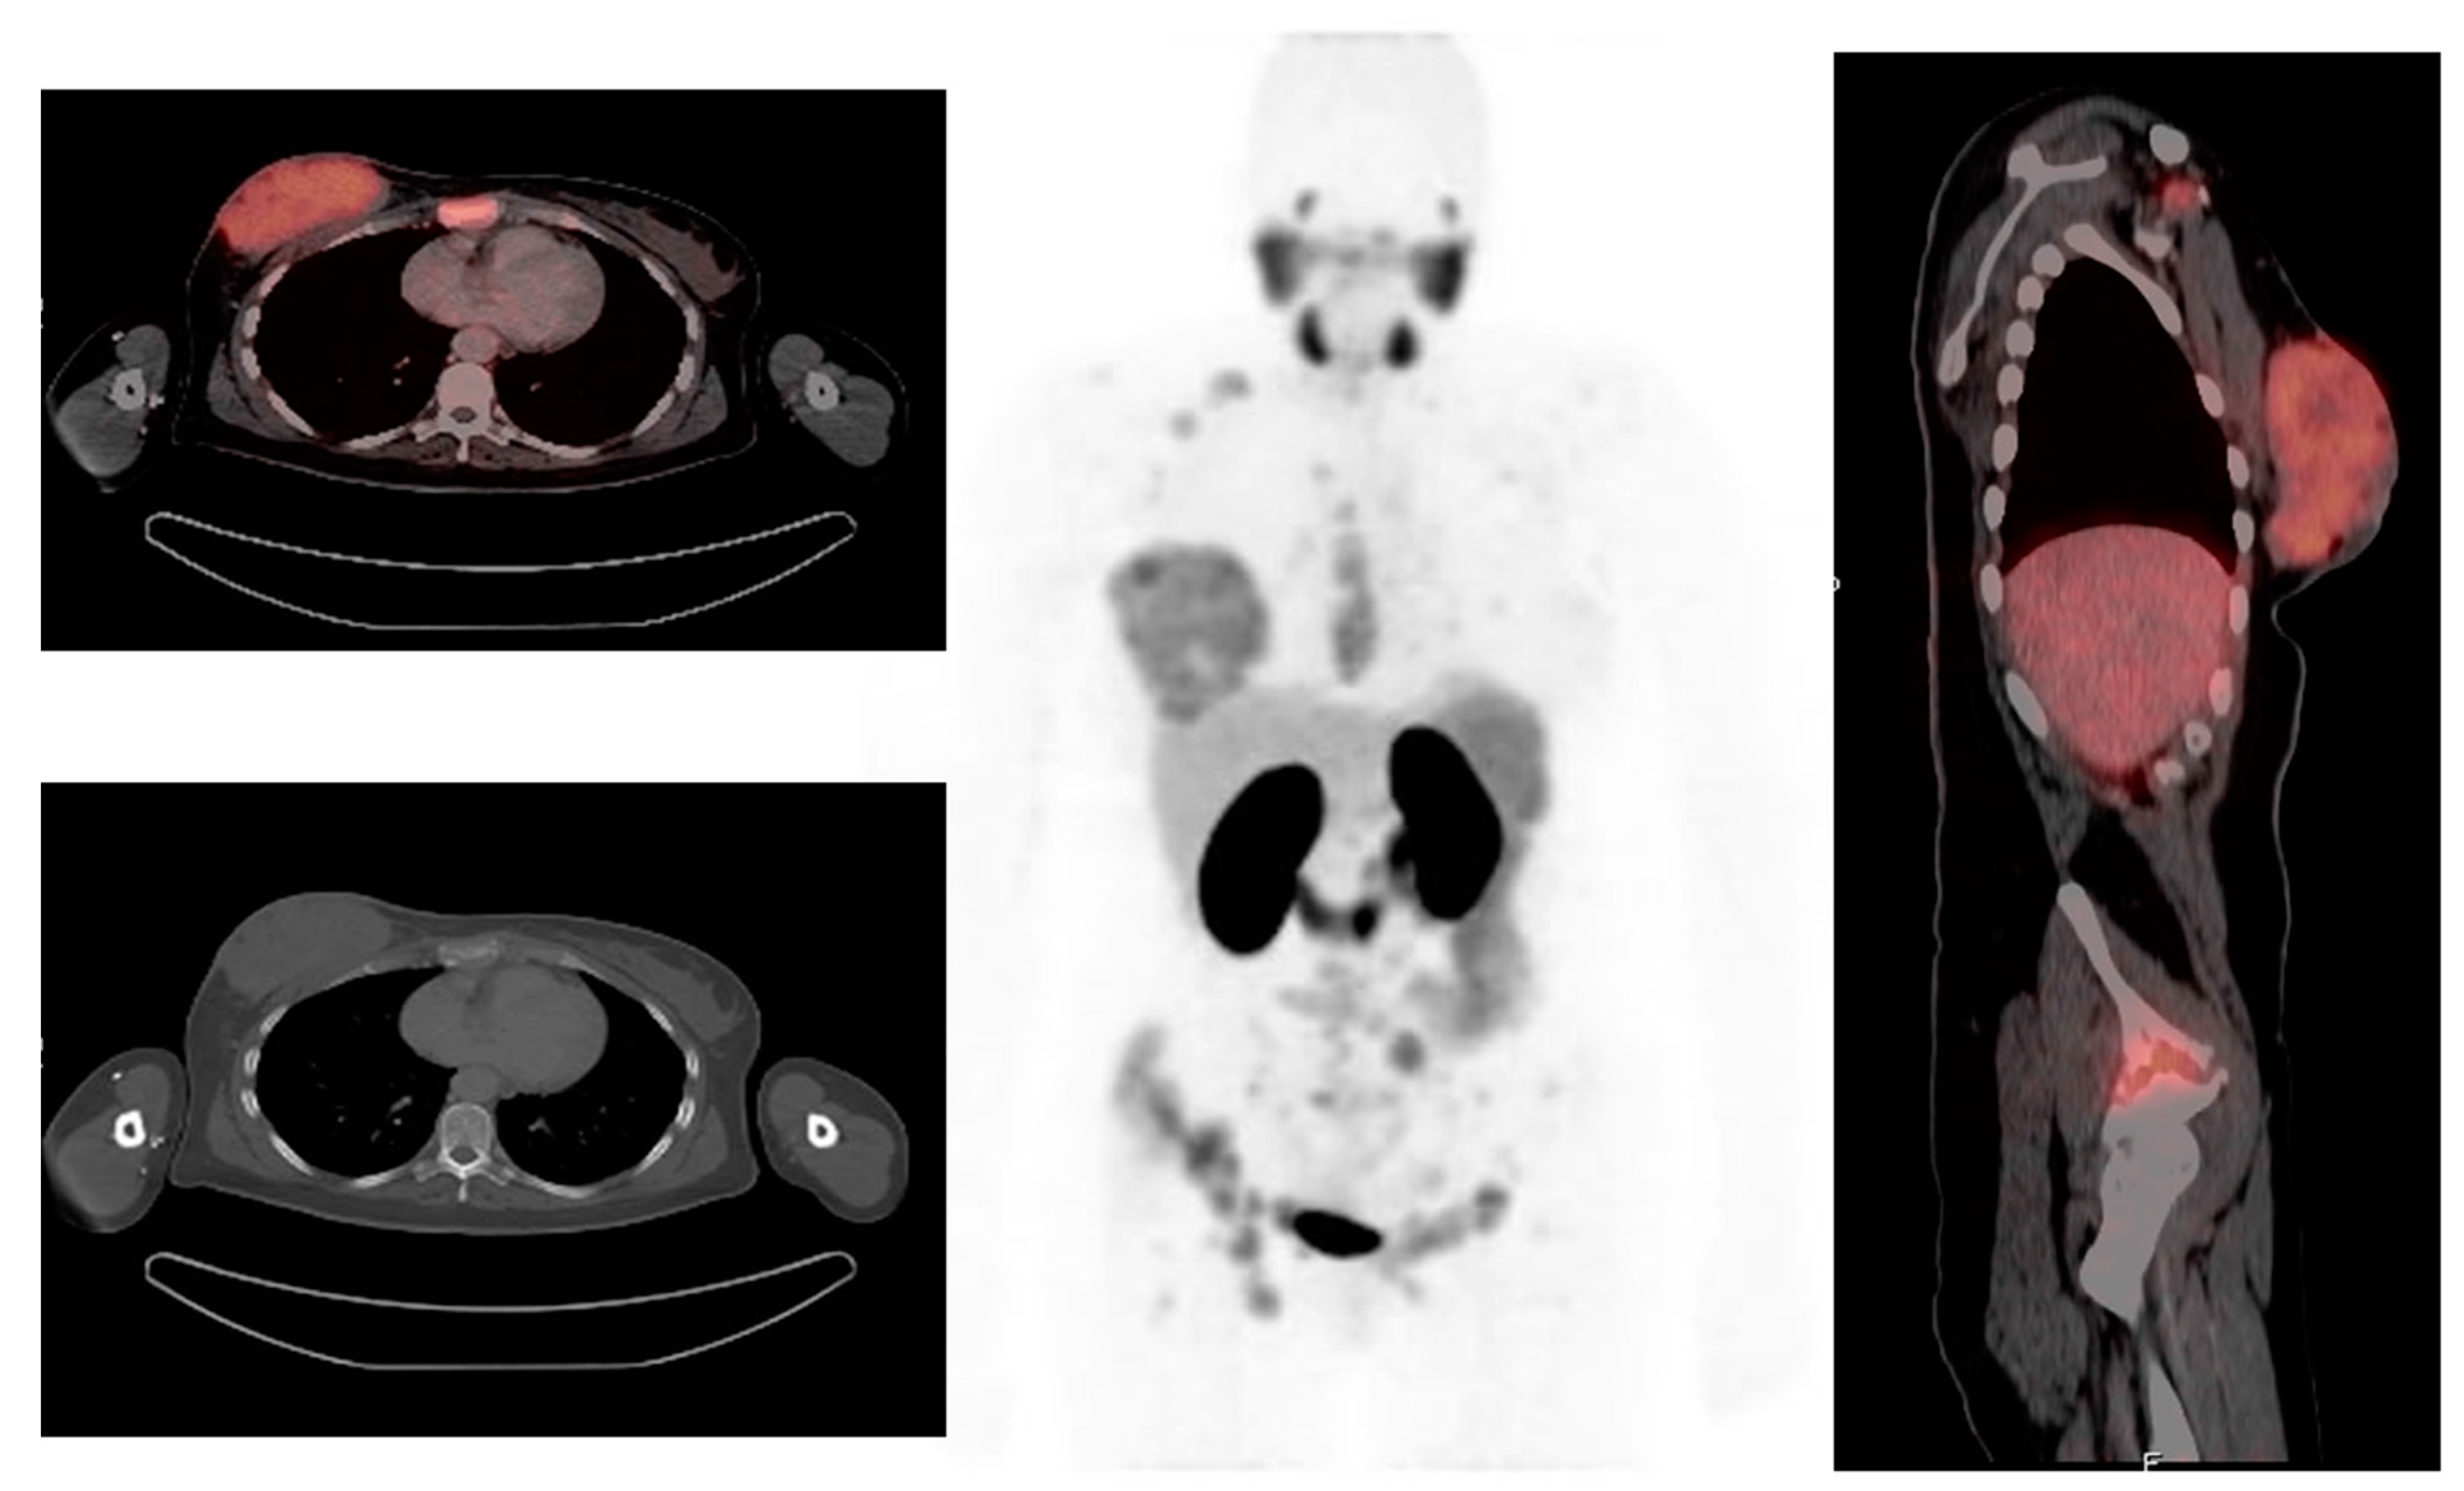

3.2. Prostate-Specific Membrane Antigen

3.3. Chemokine Receptor 4